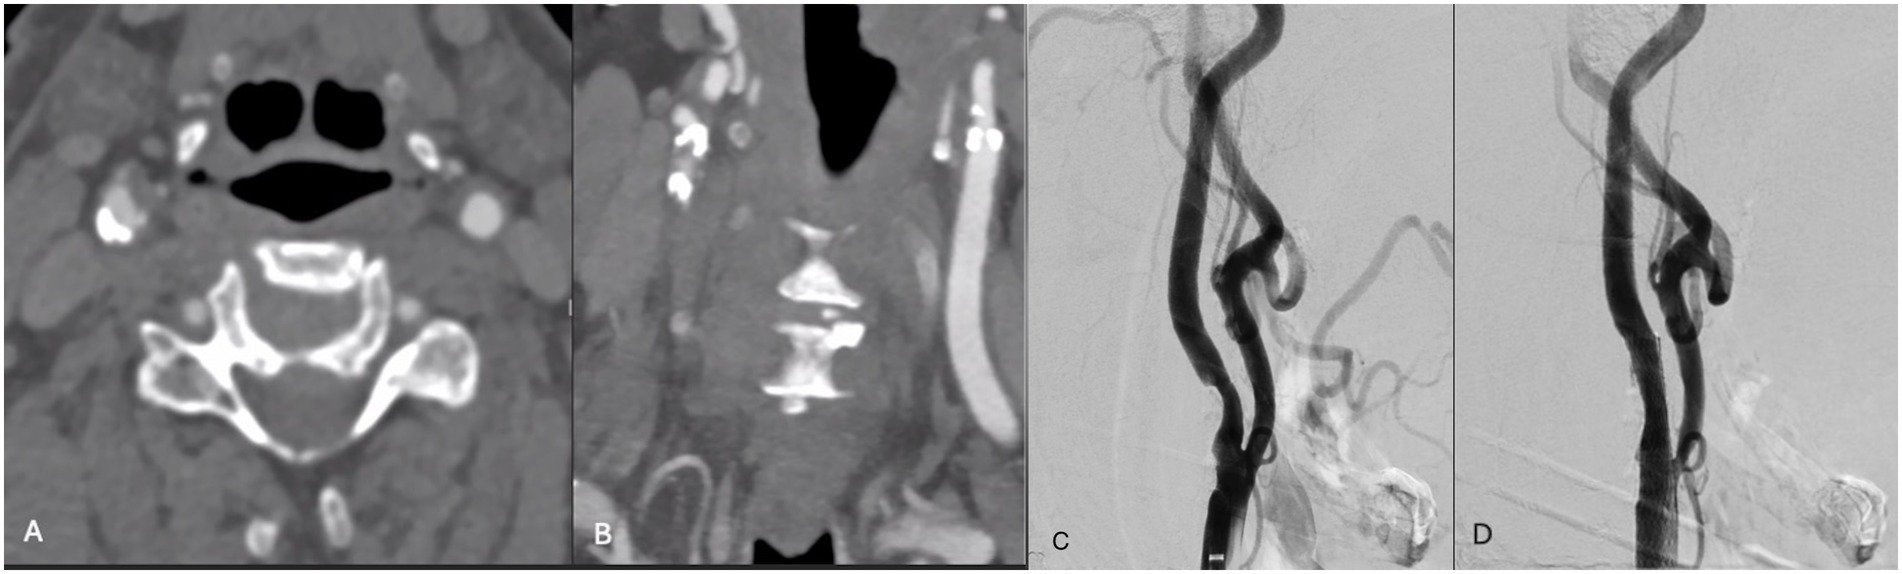

Figure 1. (A,B) Axial and coronal CTA demonstrating right ICA circumferential calcified stenosis. Catheter angiography demonstrating (C) severe R ICA stenosis with (D) significant improvement in caliber and flow within right ICA following lithotripsy, stent and angioplasty. (E,F) Axial and coronal CTA demonstrating right ICA circumferential calcified stenosis. Catheter angiography demonstrating (G) severe R ICA stenosis with (H) significant improvement in caliber and flow within right ICA following lithotripsy, stent and angioplasty.

A patient in their 80s presented with left homonymous hemianopia and dizziness (Table 1). CTA revealed greater than 80% stenosis of the right ICA. Associated right hemispheric watershed punctate infarcts were noted on diffusion-weighted MRI. The level of the carotid bifurcation with severely calcified stenosis was located high in the neck and deemed surgically accessible; therefore, CAS with concomitant IVL was recommended over CEA. One episode of sonic pulses was released over 1 min, with approximately one sonic pulse cycle per second (Figure 1). The patient was neurologically intact following the procedure. Post-angiogram ultrasound showed a peak systolic velocity (PSV) of 106 cm/s in the ICA/stent with no significant stenosis visualized within the stent. The PSV ICA/CCA ratio was 1.7 with a normal vertebral artery waveform. Following the stenting procedure, the patient experienced transient hypotension followed by left-sided drift. MRI was completed at that time, showing small foci of acute infarctions in the right frontal lobe and right corona radiata. It was found that the P2Y12 reactive unit assay suggested they were non-responders, and therefore, clopidogrel was stopped and ticagrelor was initiated. The patient was discharged to inpatient rehabilitation after an 8-day hospital stay. At the 3-week follow-up, they had no visual deficit, and the left-sided weakness had resolved. The patient was then transferred to an outside hospital for further care.

A patient in their 70s presented with a transient ischemic attack (TIA) that manifested as a right eye vision disturbance. CTA revealed 90% occluded right ICA. MRI was obtained and showed no acute infarct. Given the patient’s concurrent advanced heart failure, history of coronary artery bypass graft, and cervical laminectomy and instrumented fusion, they were deemed unfit for general anesthesia and carotid endarterectomy. IVL with stenting was performed with 2 episodes of pulses (Figure 1). Post-angiogram ultrasound showed a PSV of 102 cm/s in the right ICA with a PSV ratio of 1 in the ICA/CCA. There were no post-procedural complications, and the patient was discharged in stable condition 1 day following the procedure. At the 3-week follow-up, the patient was clinically stable with no observed or reported neurological deficits, aside from a baseline mild facial droop. However, the patient unfortunately died 7 months following the procedure secondary to an acute exacerbation of chronic heart failure.